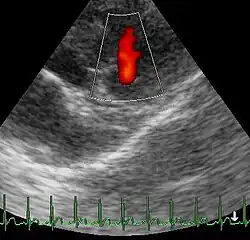

Üblich ist die Einteilung der Pulmonalklappeninsuffizienz in vier Schweregrade (Stadium I° bis IV°) in Abhängigkeit von der Blutdruckamplitude (= Pulsdruck = Pulsamplitude) bei der Rechtsherzkatheterisierung, vom Lagetyp im Elektrokardiogramm (EKG), von der Ventrikelkonfiguration im Röntgen-Thorax, von der Ventrikelgröße bei der Echokardiographie, vom Insuffizienzjet bei der Farbdoppler-Untersuchung und vom Blutrückstromvolumen bei der Herzkatheteruntersuchung. Bei dieser Einteilung wird eine Proportionalität zwischen den pathologischen Befunden und der Belastungseinschränkung unterstellt. Ein weiteres Maß für die Schwere der Insuffizienz ist die Klappenöffnungsfläche (abgekürzt KÖF).

Im Röntgenbild des Thorax oder im Kardio-MRT (Kernspintomographie) sieht man einen vergrößerten rechten Ventrikel und dilatierte Pulmonalarterien. Mit Hilfe der Farbdopplerechokardiographie und auch der Computer-Tomographie kann das Ausmaß der Insuffizienz beurteilt werden.[35] Die Diagnose wird nach einer Herzkatheterisierung und nach einer Angiokardiographie gestellt.[36]